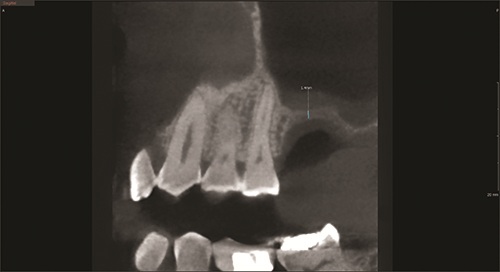

A 6.0 x 10 mm implant (Fig. 4) was placed at the facial bony crest. PRF membranes were positioned over the implant before closure with 3-0 PTFE sutures. The site was again treated with an erbium laser to de-epithelialize the surface as previously described, followed by irrigation with 30 cc of aqueous ozone.

Elevating Implant Success

Fig. 4

After three months of healing, the patient was scheduled for implant exposure (Fig. 5). Topical anesthetic was applied, followed by administration of 0.5 cc of 20 mg lidocaine with 10 mcg epinephrine, and 2.0 cc of 40 mg Septocaine with 5 mcg epinephrine.

After three weeks, the definitive abutment was soaked in aqueous ozone and seated with 30 N of force, repeated twice. The access was sealed with First Plug, and a photograph was taken of the access site. Contacts were verified, and occlusion was adjusted and polished. The crown was cemented (Fig. 6) using E-Cement (Bisco). Excess cement was removed, and a postoperative radiograph confirmed complete cleanup.

Fig. 5

Fig. 6